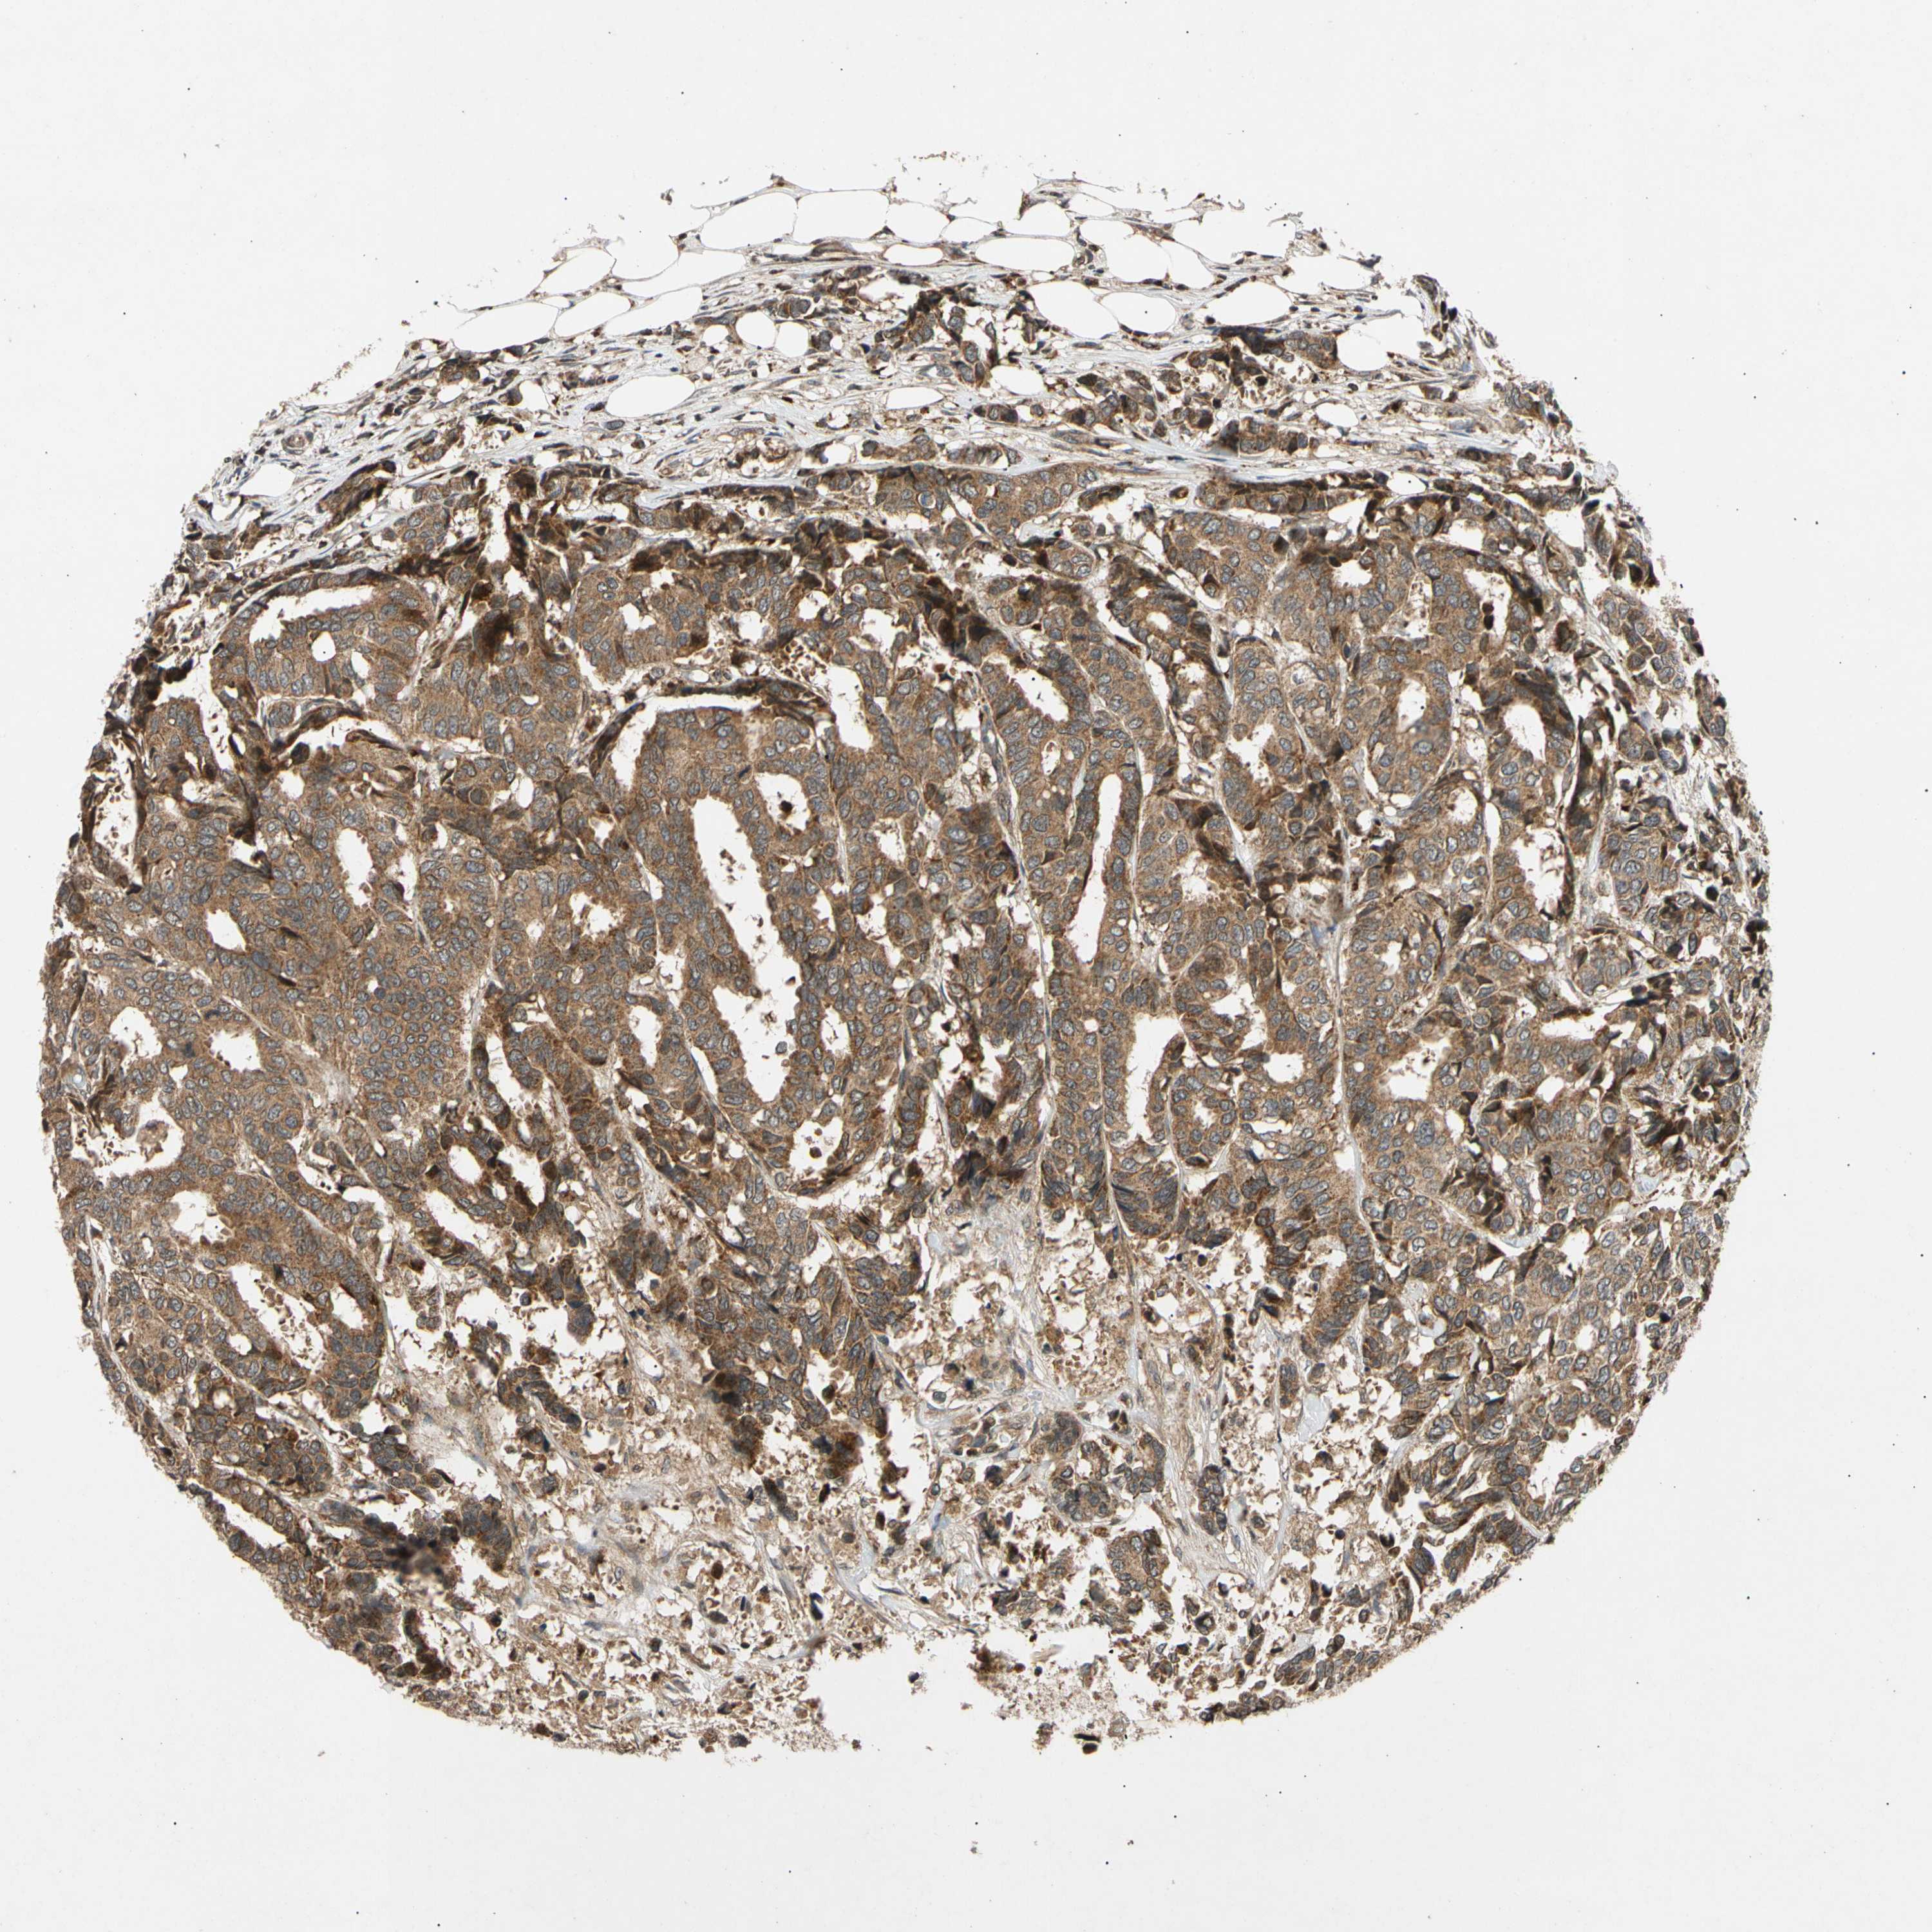

CANCER BREAST CANCER Show tissue menu

BRCA TCGA BRCA VALIDATION PROTEIN EXPRESSION

Breast cancer

Human cancer

Breast invasive carcinoma